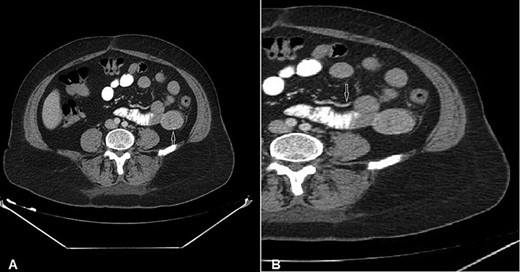

A 54-year-old woman presented with a history of multiple episodes of melaena and haematochezia accompanied by colicky abdominal pain and fatigue for the previous 3 days. Other than hypertension she did not have any other comorbidity. On primary physical examination she was pale and had a slight tachycardia but was normotensive. Abdominal examination was unremarkable. Digital rectal examination confirmed melaena stool mixed with fresh blood. Laboratory tests revealed a low haemoglobin of 7.2 g/dl. Clotting tests were normal. The patient was commenced on IV fluids and a transfusion with packed red blood cells. Emergency gastroscopy to the third part of the duodenum did not show any evidence of active bleeding. She continued to pass large amounts of melaena and fresh blood and her haemoglobin was noted to have dropped to 5.4 g/dl. A colonoscopy was decided against. She received further packed red blood cells and underwent an urgent computed tomography (CT) scan with oral and IV contrast. This showed a well-defined homogenous extraluminal mass (4 × 3.5 cm) in the proximal jejunum with mesenteric neovascularisation. There was no evidence of intra-abdominal metastases or enlarged lymph nodes (Figs 1 and 2). These findings were most suggestive of a bleeding GIST. Angiography and embolisation facilities were not available in our institution. The patient was becoming unstable and so an urgent laparotomy was required.

CT of the abdomen with Intravenous and oral contrast (A) coronal section, (B) sagittal section shows: well-defined extraluminal mass of proximal jejunum (white arrow).